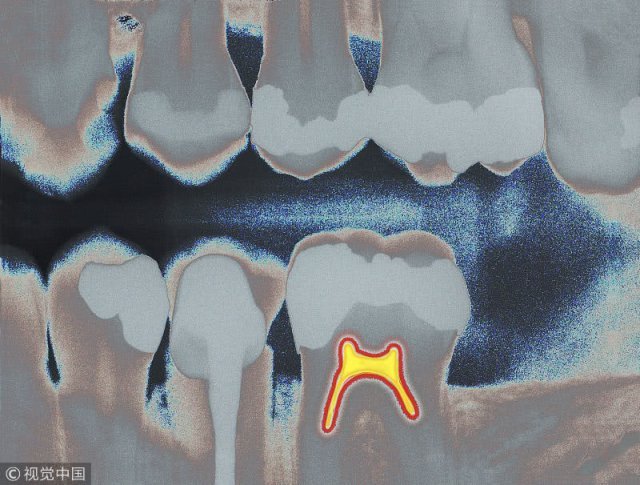

通过 CBCT,刘英志观察到,这名患者不仅口腔状况 " 糟糕 ",更是奇特的是,他的额头上竟然长着一颗 " 牙齿 "。在 CBCT 多种功能帮助下,确定该牙位于左侧筛窦内。利用 3D 重建切除部分骨,便可看到该牙斜躺着。

这一发现,令刘英志十分意外,她进一步询问患者平日里有无鼻塞、流涕等症状,这名患者立刻像遇到了 " 知音 "。他说:" 好多年了,我经常鼻塞、流涕,以及头痛。问过无数医生,都说不清怎么回事!" 刘英志说:" 病症就在你的这颗长在眉间正中位置的牙齿上!"

刘英志介绍,像这样在其他区域 " 非法生长 " 的牙齿,专业上叫做 " 埋伏牙 "。在临时实践中," 埋伏牙 " 长在上颌窦或牙槽骨等处比较常见,而像这位患者那样长在眉间正中位置的极为罕见。她提醒说,时代的进步,科技的发展,人类观念的更新,人类对于口腔的探索已不再满足于拍个片了解一下自己牙齿的外形。医学的发展,设备的进步,为治疗 " 埋伏牙 " 等口腔奇难杂症提供了强大支撑。